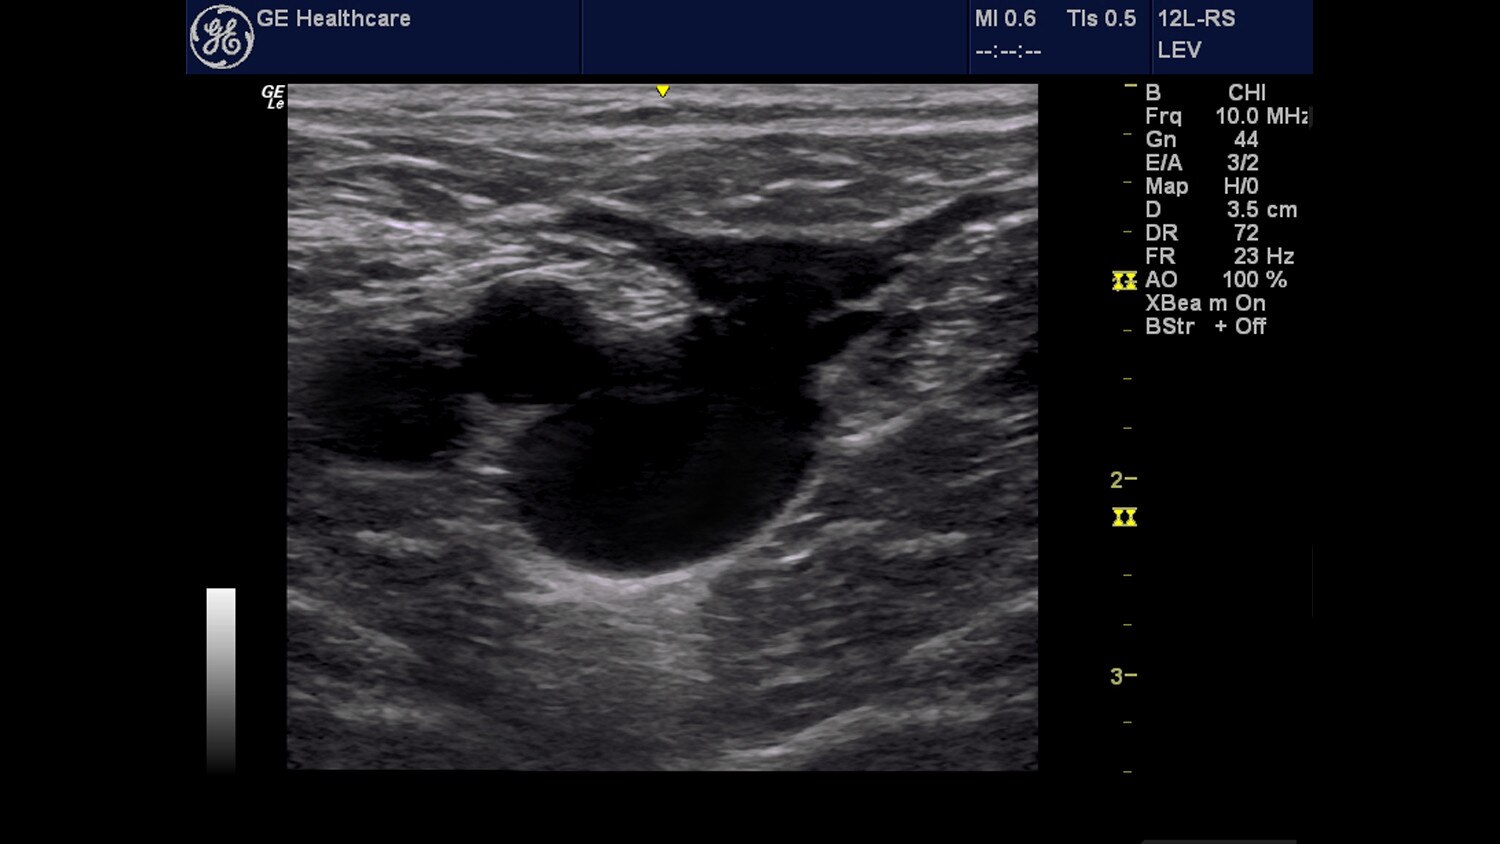

Clinical Images